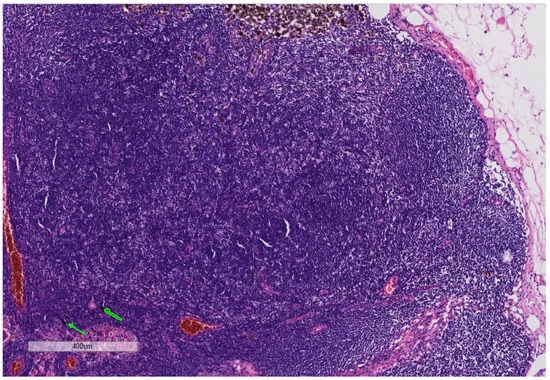

3.1. Cases with the Formation of Melanoma in Tattooed Skin

3.2. Cases with the Formation of Basal Cell Carcinoma in Tattooed Skin